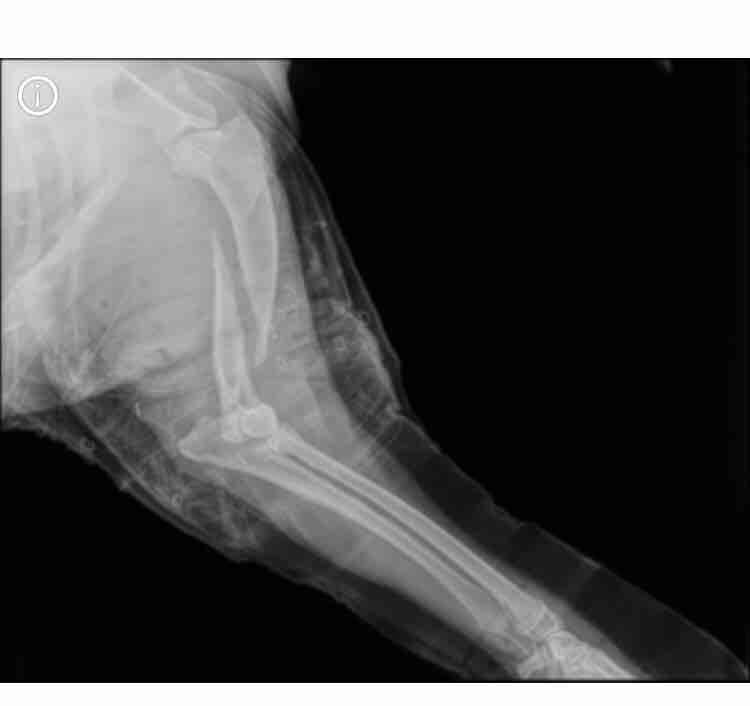

Hi What are the chances of my dogs broken mid humerus bones growing back correctly or at least partially together with a permanent splint only. Do bones shift back into place in younger dogs better. I cannot seem to afford the pins plate surgery anymore and I’m worried the oblique fracture may not heal with splint only. As long as he can regain access to his leg again and a great amount of strength in it then thatll be fine because I know it won’t be a perfect healing Based on X-ray any thoughts

Hello. I think I answered your question previously about Max, but there was no x-ray. Now seeing the pictures, there is certainly a great concern as to whether the bone will knit together with just a splint. Since orthopedic repair is out of the question, this is your only recourse. Once, many years ago, I radiographed an older lab with a shattered femur. There were multiple large pieces none of them even remotely near each other. My advice to the owners was to repair the leg with multiple pins & plates or amputate the leg. They elected to take the dog home & confine it - no splint. 2 years later, that dog walked in on his own. The leg supported his weight but was definitely bumpy & a little crooked. I will never doubt the amazing healing power of the body. I cannot guarantee that this will happen with Max, but I would definitely give it a try. If you keep him restrained, leash walk only, & if he becomes too rambunctious, consider tranquilizers ( often used in difficult orthopedic repairs when the patient just will not behave himself ), he may heal just fine. If you have not considered CareCredit, you might check them out. It is a medical credit card that most veterinarians accept & may allow you to pay off the surgery over a 6-12 month period, or even longer. Max is young & healthy. It is amazing how the body will heal itself. Good luck & thanks for using Petco Pet Education Center, formerly Petcoach.

HI, thanks for using Petco Pet Education Center, formerly Petcoach! Poor Bailey! The picture of the X-ray you provided looks like a radius/ulnar fracture. If your Vet could sedate Bailey and try to get better alignment of the fracture, it COULD possibly heal with just a splint. You would need to strictly rest her for 6-8 weeks, be able to bring her back frequently for splint changes and repeat X-rays and be prepared for it to not heal well. It may be worth a shot. Please though trust your Vet's opinion he/she knows best because they have seen your dog and know her history! Good luck!